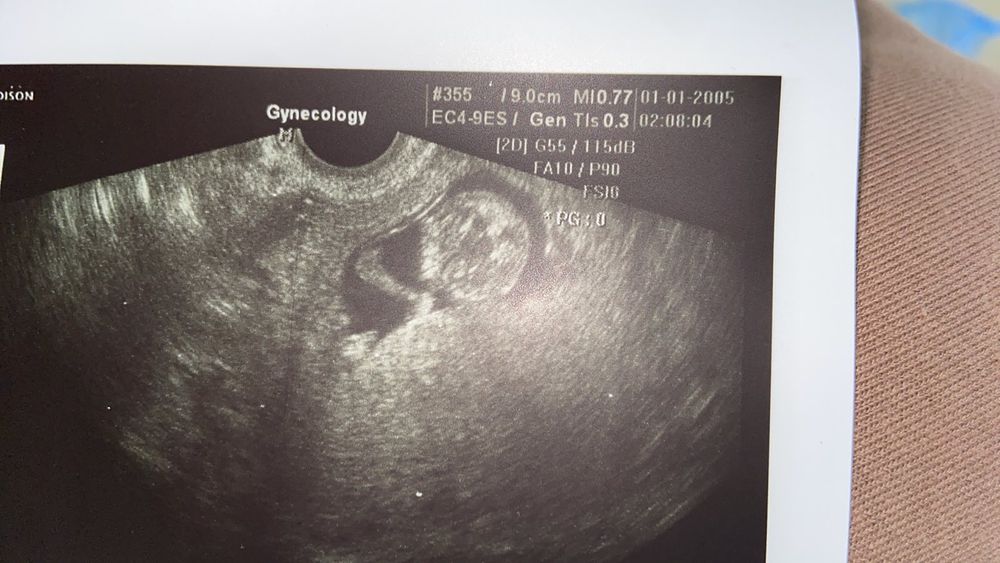

Наши будни, наши недельки11.10 2022 я была на приеме у гинеколога… Ляля подросла 50мм уже… пока по ктр так и опережаем срок по мес…гематому уже не увидели… малышарик спал… редко подёргивая ножкой и сосал палец:)

первый скрининг 01.11.22. Будет уже 12 недель и 5 дней… надеюсь пол скажут…